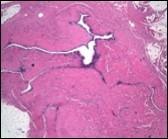

Figure 5.Cutaneous ciliated cyst with incomplete intervening septa and a lining of attenuated, ciliated epithelium along with supporting fibrous tissue (13).

Morphological analysis preponderantly demonstrates a solitary, uni-locular or multi-locular cyst of Mullerian origin with an epithelial lining recapitulating the epithelium of fallopian tube.

Cystic structures cogitated within deep dermal or subcutaneous tissue can be impacted with haemorrhagic fluid. Cyst lining is smooth, regular and is essentially composed of a singular layer of columnar epithelium with focally pseudostratified columnar epithelium, a circumscription of loosely configured, well vascularized, fibroconnective or fibrocollagenous tissue and an absence of inflammatory infiltrate.